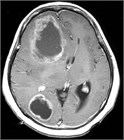

1. 定位照射+全脳照射併用療法は、治療後3~4カ月でも高次脳機能障害のリスクが高いことが明らかで、初回治療としては全脳照射を併用せず、定位照射のみを行い、頻回に経過観察を行うことが推奨される(推奨度3)